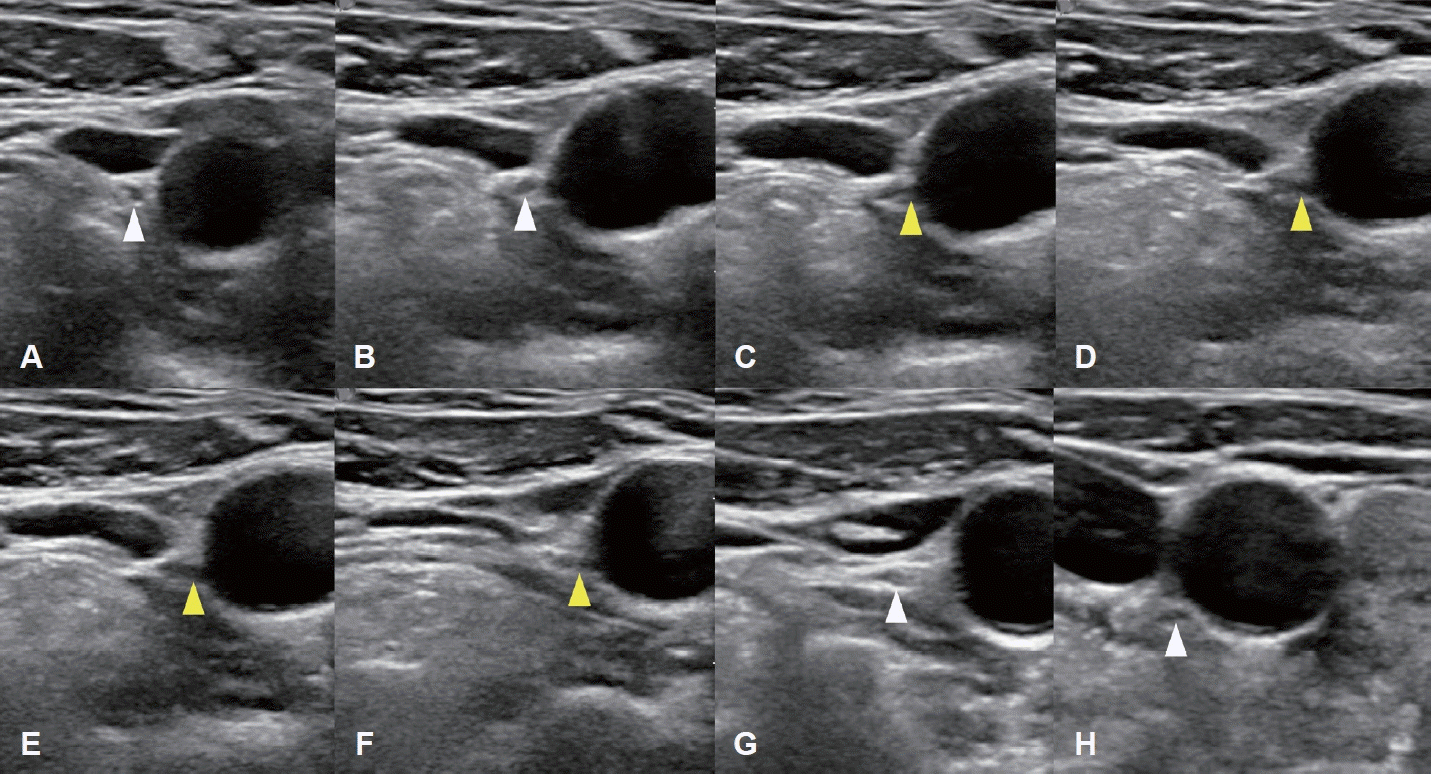

Fig. 2.

Serial ultrasonographic tracking images of the NRLN obtained using a 5–12 MHz linear-array transducer. A-F: A series of transverse ultrasound images arranged in craniocaudal order shows the suspected right NRLN (yellow arrowheads). A and B: The right vagus nerve (white arrowheads) is visualized between the IJV and CCA at the level of thyroid cartilage. C and D: A nerve branch is seen arising directly from the right vagus nerve. E and F: The nerve branch courses horizontally and medially toward the CCA. G and H: The descending vagus nerve (white arrowheads), separated from the NRLN, is seen at the level of the cricoid cartilage and thyroid gland. This direct, non-recurrent path from the right vagus nerve at the level of the larynx is highly suggestive of an NRLN. NRLN, non-recurrent laryngeal nerve; IJV, internal jugular vein; CCA, common carotid artery.